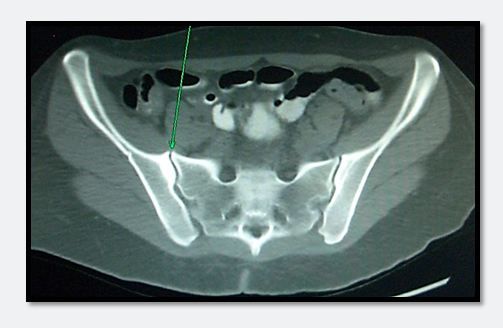

Figure 2.

The image of the abdominal CT in Figure 2 shows sacroiliitis (green arrow), which when it co-occurs with bloody diarrhea is highly suspicious for inflammatory bowel disease (IBD). The patient was eventually diagnosed with ulcerative colitis (UC).